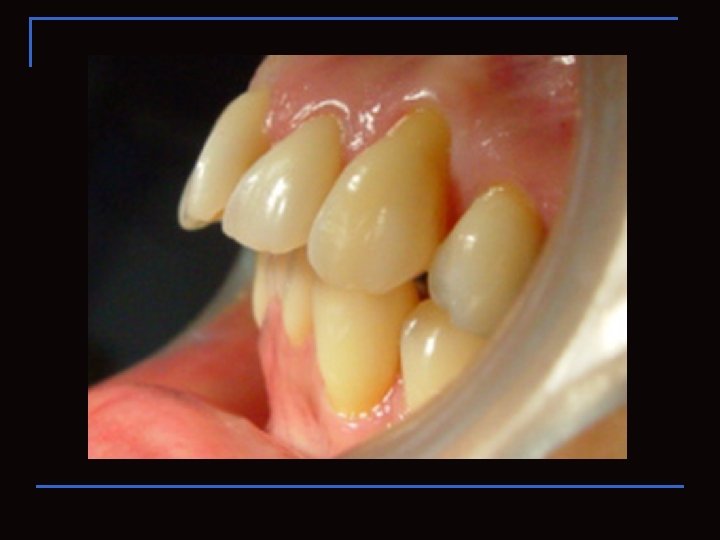

Región Vestibular